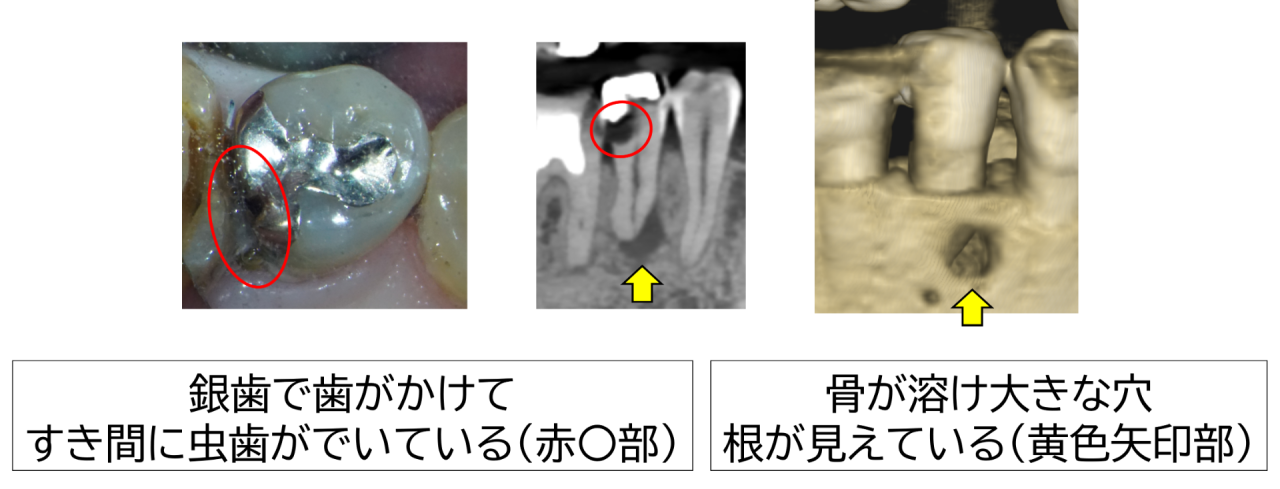

診察すると、過去に装着された銀歯が硬く、長年の噛み合わせによって歯の一部に細かいヒビや欠けが生じていました。その微細な隙間から虫歯菌が入り込み、二次的な虫歯が進行。レントゲン検査では虫歯が神経まで達し、歯の根の先端付近で炎症により顎の骨が大きく吸収している像が確認されました。いわゆる「骨が溶けている」状態です。感覚検査でも温刺激で強い痛みが長く続き、不可逆性歯髄炎の典型的な所見でした。歯ぐきにはできものもできており、骨が突き破られるほど進行していました。

今回のように銀歯が硬く歯を割ったり欠けさせたりすることで隙間ができ、そこから虫歯菌が入り込むケースでは、見た目では気づきにくく、気づいたときには神経にまで感染が及んでいることがあります。定期的な検診と被せ物の適合チェックが再発防止には欠かせません。

今回の症例では、硬い銀歯が歯にヒビや欠けを生じさせ、その隙間から虫歯菌が侵入し、神経に炎症が起き、さらに顎の骨が溶けてできものができるくらい大きく吸収されていました。